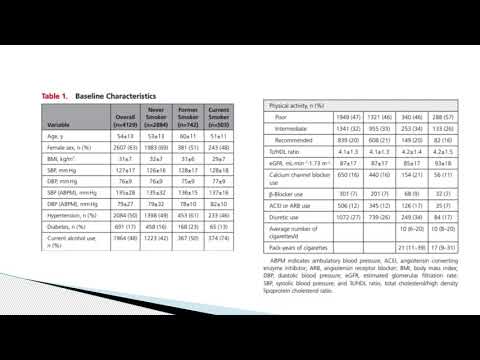

Caracteristicas basales y perfiles de riesgo de los participantes del estudio ISCHEMIA. Dra. Carolina G. Reynoso. Residencia de Cardiología. Hospital C. Argerich. Buenos Aires